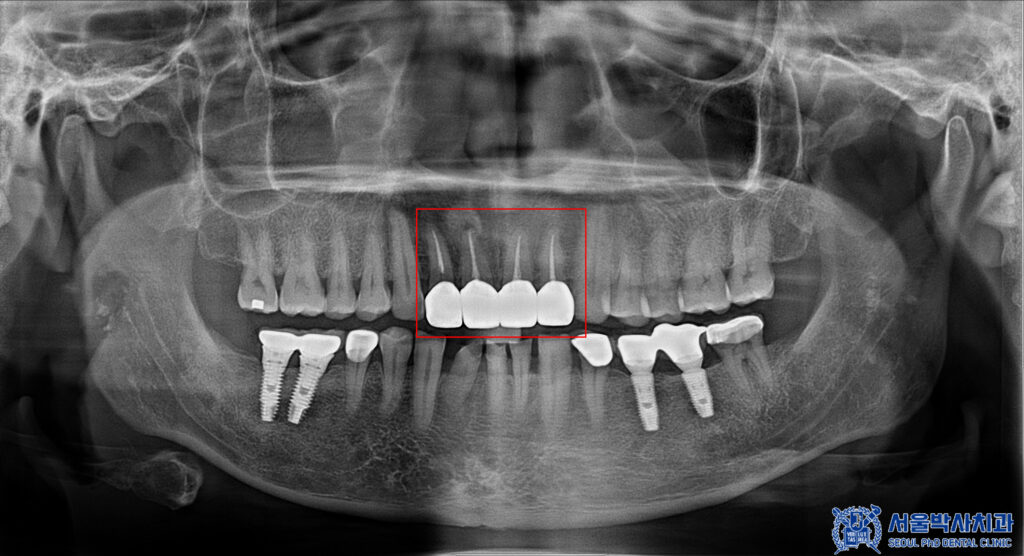

파노라마를 촬영하고

확인해 보았을 때도,

보철물이 방사선불투과성이라

치아 내부를 정밀하게

확인할 수 없었습니다.

그래서 산성동치과 서울박사치과에서는

해당 브릿지를 제거하여

내부 상황을 확인하기로

환자분과 상의 후 결정하였습니다.

제거를 하고 확인해 보니,

내부로 충치가 생긴 것을

확인할 수 있었습니다.